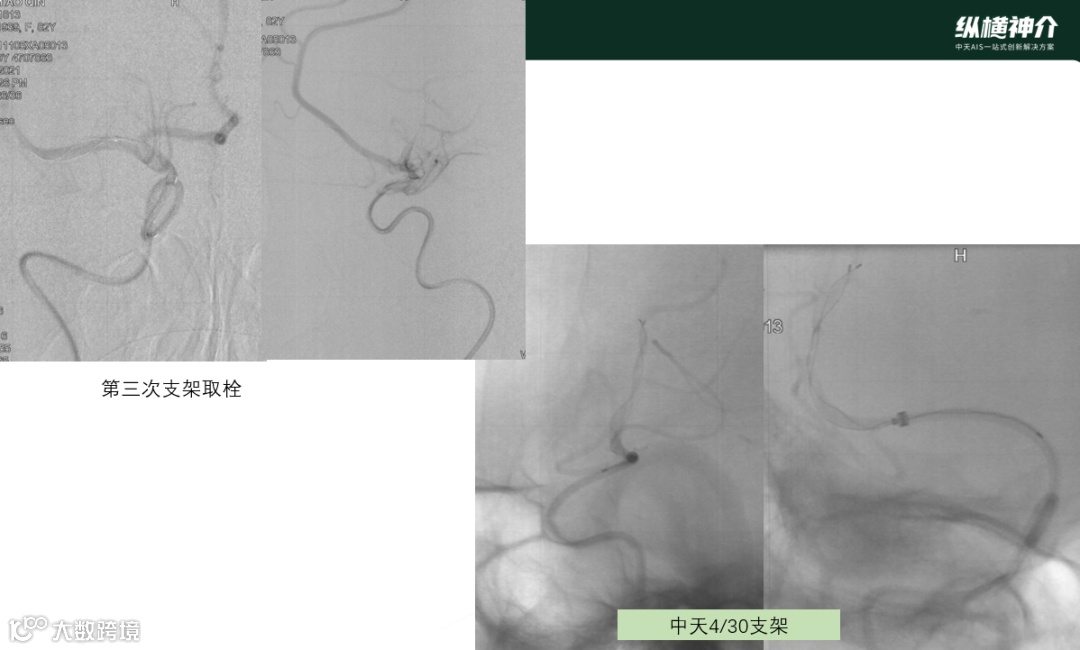

• 第三次取栓

• 天弋®取栓支架 4*30mm

• 抓捕的血栓效果来看,血栓是一个旋转的形态,用手去取下支架上的血栓比较难以取下,需要把血栓碾碎后取下。支架与血栓粘结非常紧密,临床表现优异